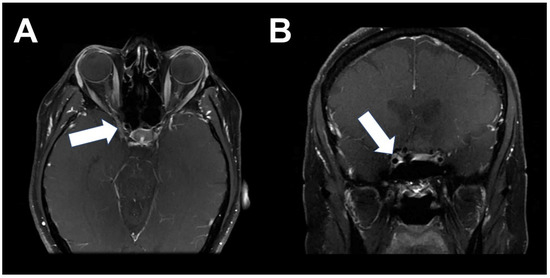

2. Case 1